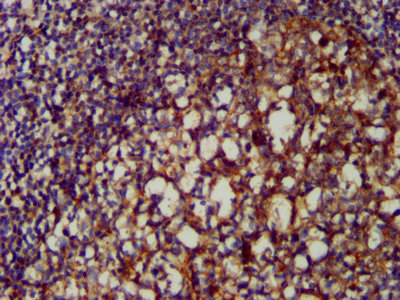

IHC image of CSB-PA06029A0Rb diluted at 1:200 and staining in paraffin-embedded human endometrial cancer performed on a Leica BondTM system. After dewaxing and hydration, antigen retrieval was mediated by high pressure in a citrate buffer (pH 6.0). Section was blocked with 10% normal goat serum 30min at RT. Then primary antibody (1% BSA) was incubated at 4°C overnight. The primary is detected by a biotinylated secondary antibody and visualized using an HRP conjugated SP system.

IHC image of CSB-PA06029A0Rb diluted at 1:200 and staining in paraffin-embedded human tonsil tissue performed on a Leica BondTM system. After dewaxing and hydration, antigen retrieval was mediated by high pressure in a citrate buffer (pH 6.0). Section was blocked with 10% normal goat serum 30min at RT. Then primary antibody (1% BSA) was incubated at 4°C overnight. The primary is detected by a biotinylated secondary antibody and visualized using an HRP conjugated SP system.